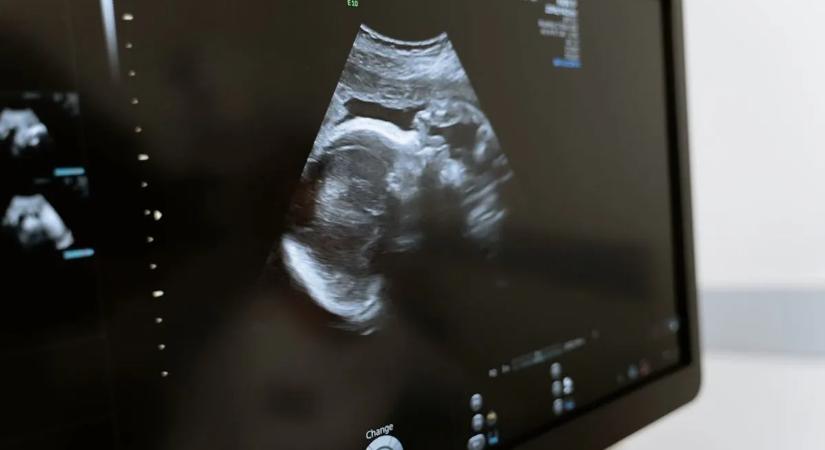

Az utolsó ultrahangot végezték a kismamán – majd hirtelen rémisztő csend lett a szobában

Sokkot kapott az anya. Az ultrahang rettenetes dolgot árult el.